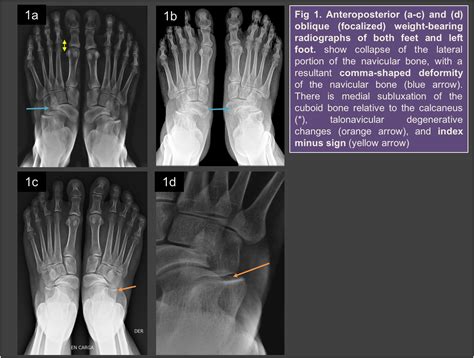

Mueller Weiss Syndrome is a rare degenerative disease of the navicular bone, a small, boat-shaped bone located in the midfoot. Unlike fractures caused by acute trauma, this syndrome occurs when the bone loses its blood supply, leading to fragmentation and collapse. While the exact cause remains somewhat elusive, it is frequently associated with mechanical stress, congenital anomalies, or systemic conditions that impede vascular flow.

Typically, the syndrome affects adults between the ages of 40 and 60. Patients often present with persistent pain on the inner (medial) side of the foot, which gradually worsens with weight-bearing activities. As the navicular bone begins to collapse, the structural integrity of the foot’s arch is compromised, often leading to a secondary flatfoot deformity.

• Visible Deformity: A noticeable flattening of the arch or a bulging prominence in the midfoot area.

Diagnosing Mueller Weiss Syndrome requires a comprehensive evaluation by a foot and ankle specialist. Because the symptoms can mimic other conditions like tarsal coalition or arthritis, imaging is essential for a precise diagnosis.

X-ray (Weight-bearing) The primary tool to visualize the navicular bone's fragmentation and collapse.